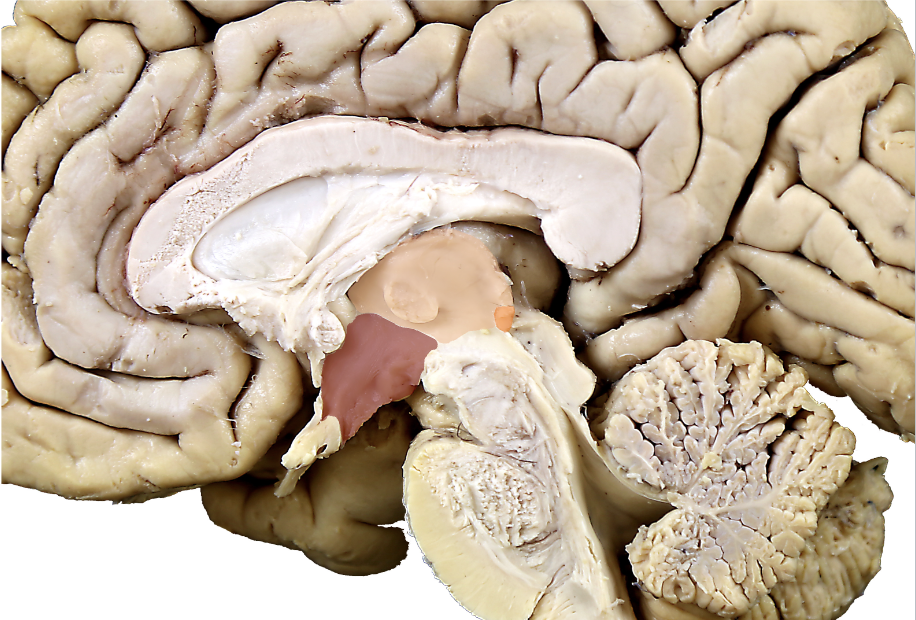

what structure is in orange?

epithalamus (pineal gland and habenula)

what structure is in red?

hypothalamus

what structure is in pink?

thalamus